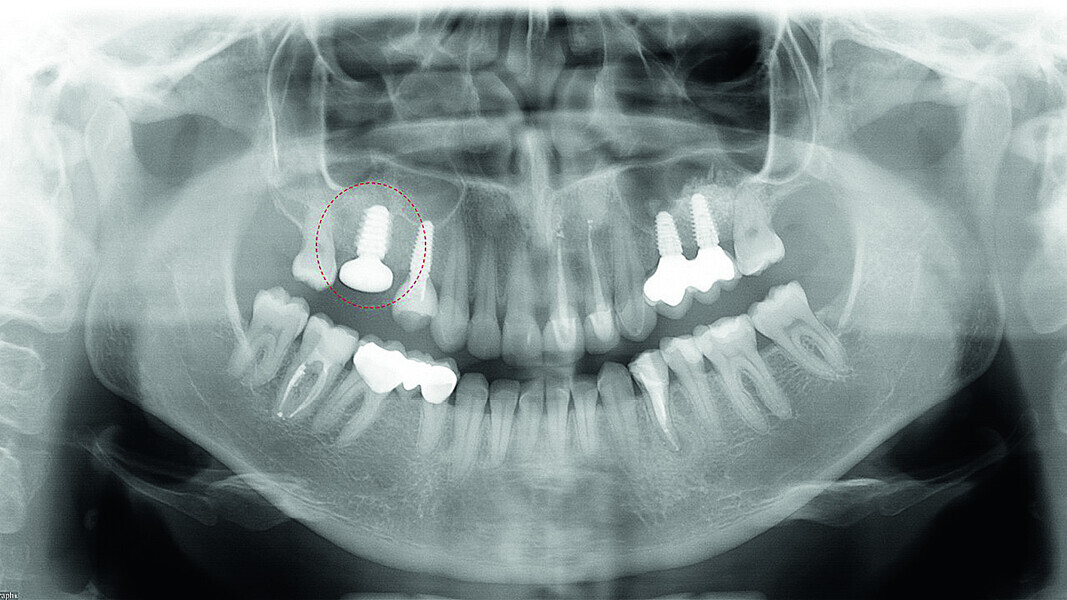

Digital workflow and application of PRF and ozone therapy in oral rehabilitation